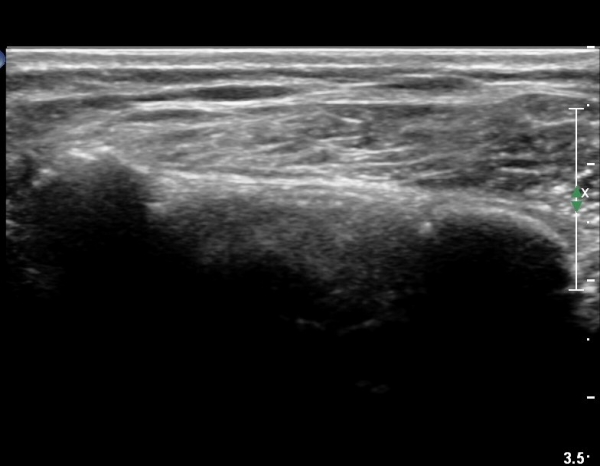

¿À±¸µ¹±â°ßºÀÀδë Á¾´Ü¸é°Ë»ç¿¡¼­ ƯÀÌ ¼Ò°ßÀ» º¸ÀÌÁö ¾ÊÀ¸³ª(»çÁø 1)